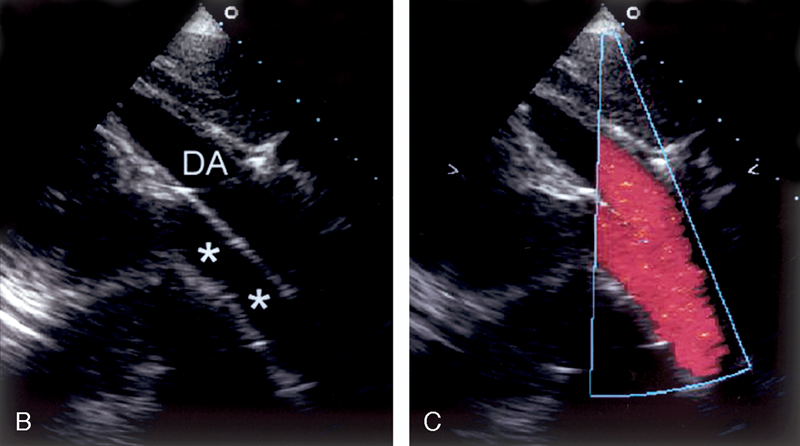

فحوصات تشخيصية لبعض امراض القلب والشرايين التاجية